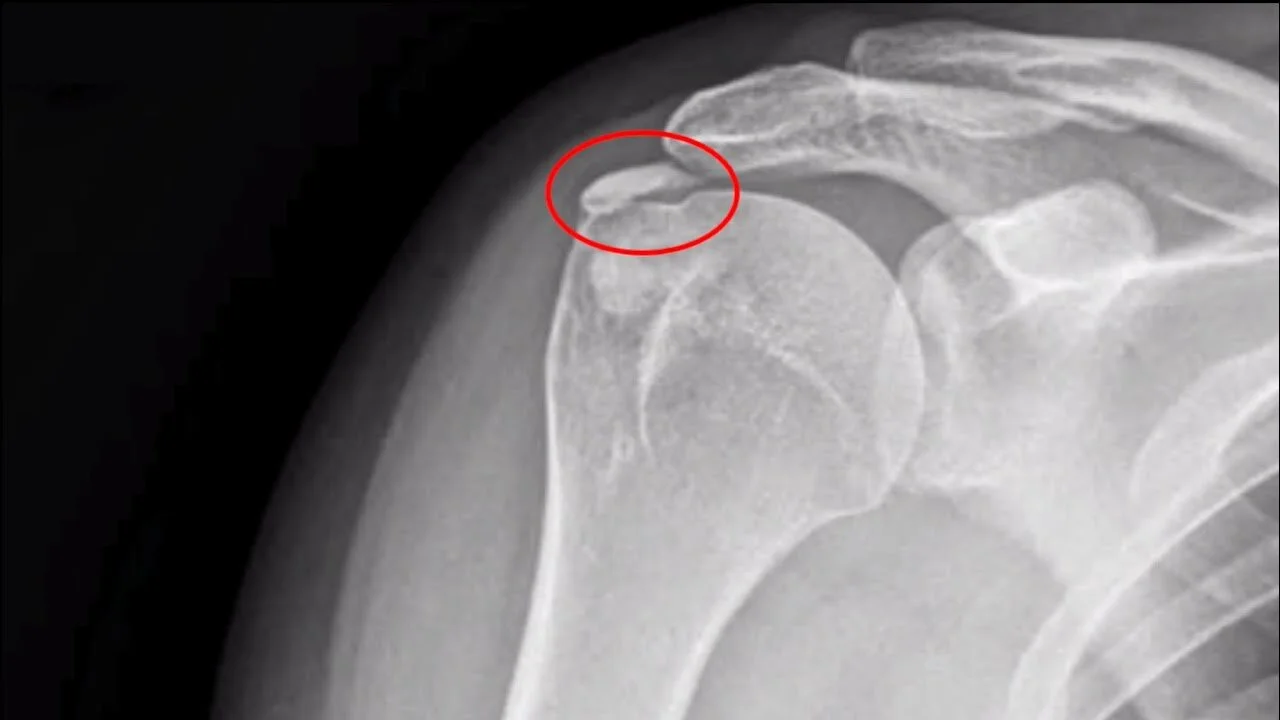

Specialista in Ortopedia e Traumatologia

Il Dottor Mario Menna è medico specialista in ortopedia e traumatologia e si occupa prevalentemente di chirurgia ortopedica e traumatologica, chirurgia protesica, chirurgia mini-invasiva (artroscopia) e medicina rigenerativa.